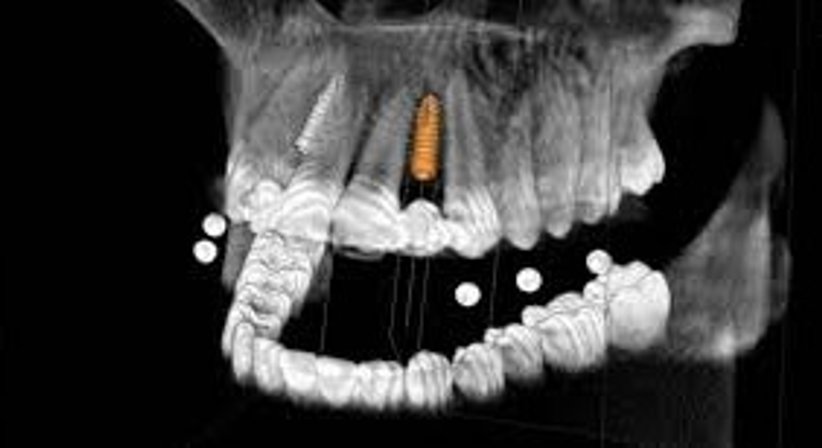

Die Praxis ist mit einem digitalen 3D Röntgen ausgestattet (digitale Volumentomographie, DVT).

Neben klassischen Implantationstechniken bieten wir Patienten die computergestützte Implantationstechnik an. Hierfür wird der Knochen dreidimensional dargestellt, was es ermöglicht, den Zahn virtuell in die ideale Position zu stellen und das Implantat in dieser zu planen. Dadurch wissen wir bereits vorab, ob an der jeweiligen Implantationsstelle ausreichend Knochenmaterial in guter Qualität vorhanden ist.

Dank computernavigierter Implantologie können Implantationen sehr genau und vorausschauend geplant werden, das vorhandene Knochenangebot wird optimal genutzt und ein Knochenaufbau kann in einigen Fällen vermieden werden.